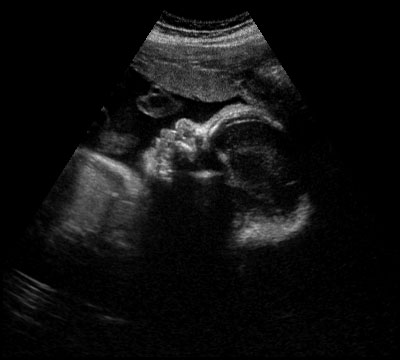

One last ultrasound image, this one in TWO dimensions.